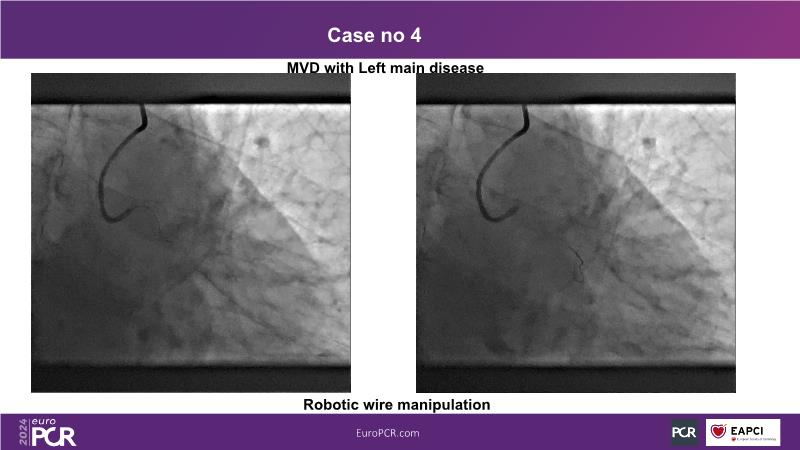

In this session, discover the effectiveness and safety of robotic PCI for both simple and complex lesions requiring additional devices like IVL, IVUS, laser, and FFR. Learn about the numerous benefits of robotics for patients and cathlab teams, including enhanced precision in wire navigation and stent positioning, full radioprotection, and reduced orthopedic injuries. Explore the growing interest in robotics within the interventional cardiology community, anticipate future technical advancements, and understand how AI will accelerate the integration of robotics and vice versa.